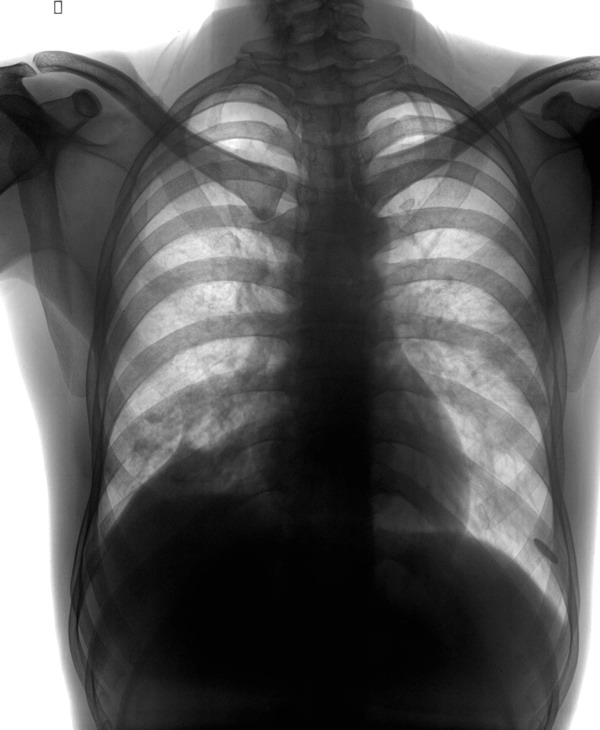

男,34y,发热寒颤月余,脓痰!

右下肺沿支气管的小结结影,还发现粘连性改变,侧位可见后肋隔角消失,因此考虑:支气管肺炎,脓旬,包裹性积液

右下肺沿支气管的小结结影,还发现粘连性改变,侧位可见后肋隔角消失,因此考虑:支气管肺炎,脓胸,包裹性积液

颈肋.右肺下叶后基底段及左肺下叶背段炎变伴右侧胸腔包裹性积液

右下肺炎,右侧胸膜肥厚,右侧胸腔积液,双侧颈肋.

右肺下叶肺脓肿并胸腔积液

右肺下叶肺脓肿并胸腔积液,胸膜粘连.左肺炎症.颈肋.

1 双侧颈肋.  2右下肺炎,3左上叶前段节段性肺炎4右侧叶间积液?

右下肺炎,包裹性积液

右下肺炎症,拌肺底积液